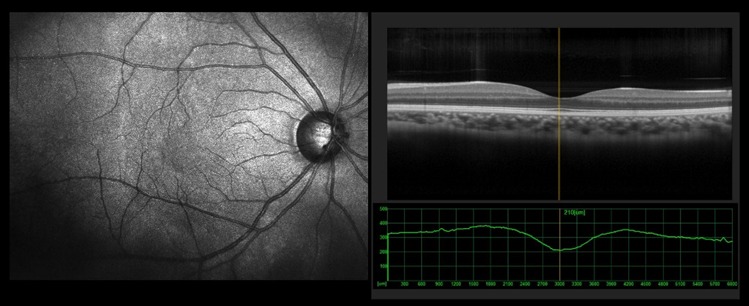

Optical Coherence Tomography (OCT) for high-resolution retinal imaging

Early detection of silent retinal diseases

Management of diabetic macular edema

Management of Age-related Macular Degeneration (AMD)

Treatment of macular holes and epiretinal membranes

Personalized care for central vision problems

Macular Degeneration

Macular Hole

Epiretinal Membrane